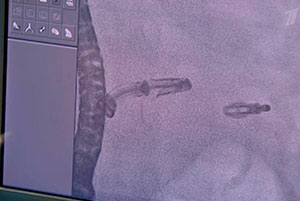

Национальный медицинский исследовательский центр кардиологии имени академика Чазова успешно лечит самые серьезные патологии, в том числе недостаточность клапанов — аортального и митрального, а с прошлого года еще и трикуспидального. Во многом благодаря нацпроекту «Новые технологии сбережения здоровья».

Комментируют руководитель отдела ультразвуковых методов исследования НМИЦ кардиологии им. ак. Е.И. Чазова Минздрава России Марина Саидова, руководитель лаборатории гибридных методов лечения ССЗ НМИЦ кардиологии им. ак. Е.И. Чазова Минздрава России Тимур Имаев, волонтер-медик по Калининградской области Карина Гзирян и координатор ВОД «Волонтеры-медики» по Республике Мордовия Варвара Терехина.